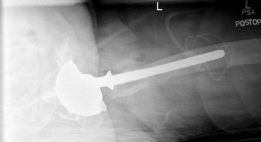

- الأشعة السينية (Radiographs): تُعد أشعة الحوض الأمامية الخلفية القياسية، وأشعة الورك الجانبية الحقيقية، وأشعة الفخذ بالطول الكامل ضرورية. تُوفر هذه الأشعة تقييمًا أساسيًا لوضع الغرسة وسلامتها وتقييمًا أوليًا لعيوب العظم. يُمكن أن تُساعد الأشعة المقارنة للورك المقابل في تحديد الأبعاد وفهم اختلاف طول الساق.

التصوير المقطعي المحوسب (CT Scan):

يُعد التصوير المقطعي المحوسب بتقنية تقليل تشوه المعدن (MARS) لا يُقدر بثمن. يُوفر معلومات مفصلة ثلاثية الأبعاد حول مدى وشكل عيوب العظم، مما يُساعد في التصنيف الدقيق لعيوب بابروسكي لكل من مفصل الحوض وعظم الفخذ. يُساعد في تحديد العيوب التجويفية مقابل العيوب القطعية، وتقييم سلامة الأعمدة، وتحديد مناطق النوافذ القشرية أو ترقق القشرة. تُوجه هذه المعلومات اختيار دعامات أو أقماع أو أكمام المعدن عالي المسامية المحددة. يُمكن للأستاذ الدكتور محمد هطيف استخدام هذه الصور لتحديد أفضل خطة جراحية.